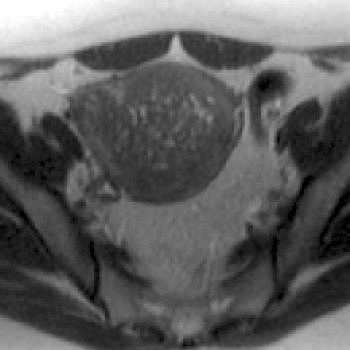

![]() |

| A 44-year-old woman with asymmetric diffuse adenomyosis. T2-weighted axial image obtained before UAE showed asymmetric diffuse thickening of junctional zone with multiple high-signal-intensity foci within that zone, which is compatible with adenomyosis. |